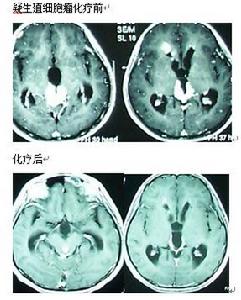

六、試驗性化療

以順鉑(PDD)為基礎的化療對顱內生殖細胞瘤有極好的效果。國外方案有PVB(PDD+VBR+Ble),PE(PDD+Vp-16),CE(Carboplatin+Vp-16)。天壇醫院從1993年開始生殖細胞瘤化療,藥物為順鉑、甲氨喋呤(MTX)、長春新鹼(VCR)和平陽黴素(Pen),可稱為VMPP方案,此方案運用至今,已治療病例數超過1000人,效果良好。

臨床疑NG-MGCTs且AFP陽性患者可採用PEB,VIP等方案,化療目的:判斷腫瘤對化療的敏感性,決定下一步治療方案。見圖。松果體區生殖細胞瘤